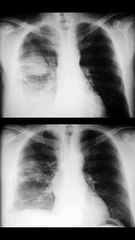

HATİCE ŞİMŞEK ( İÇ DAMAKTA TÜMÖR )